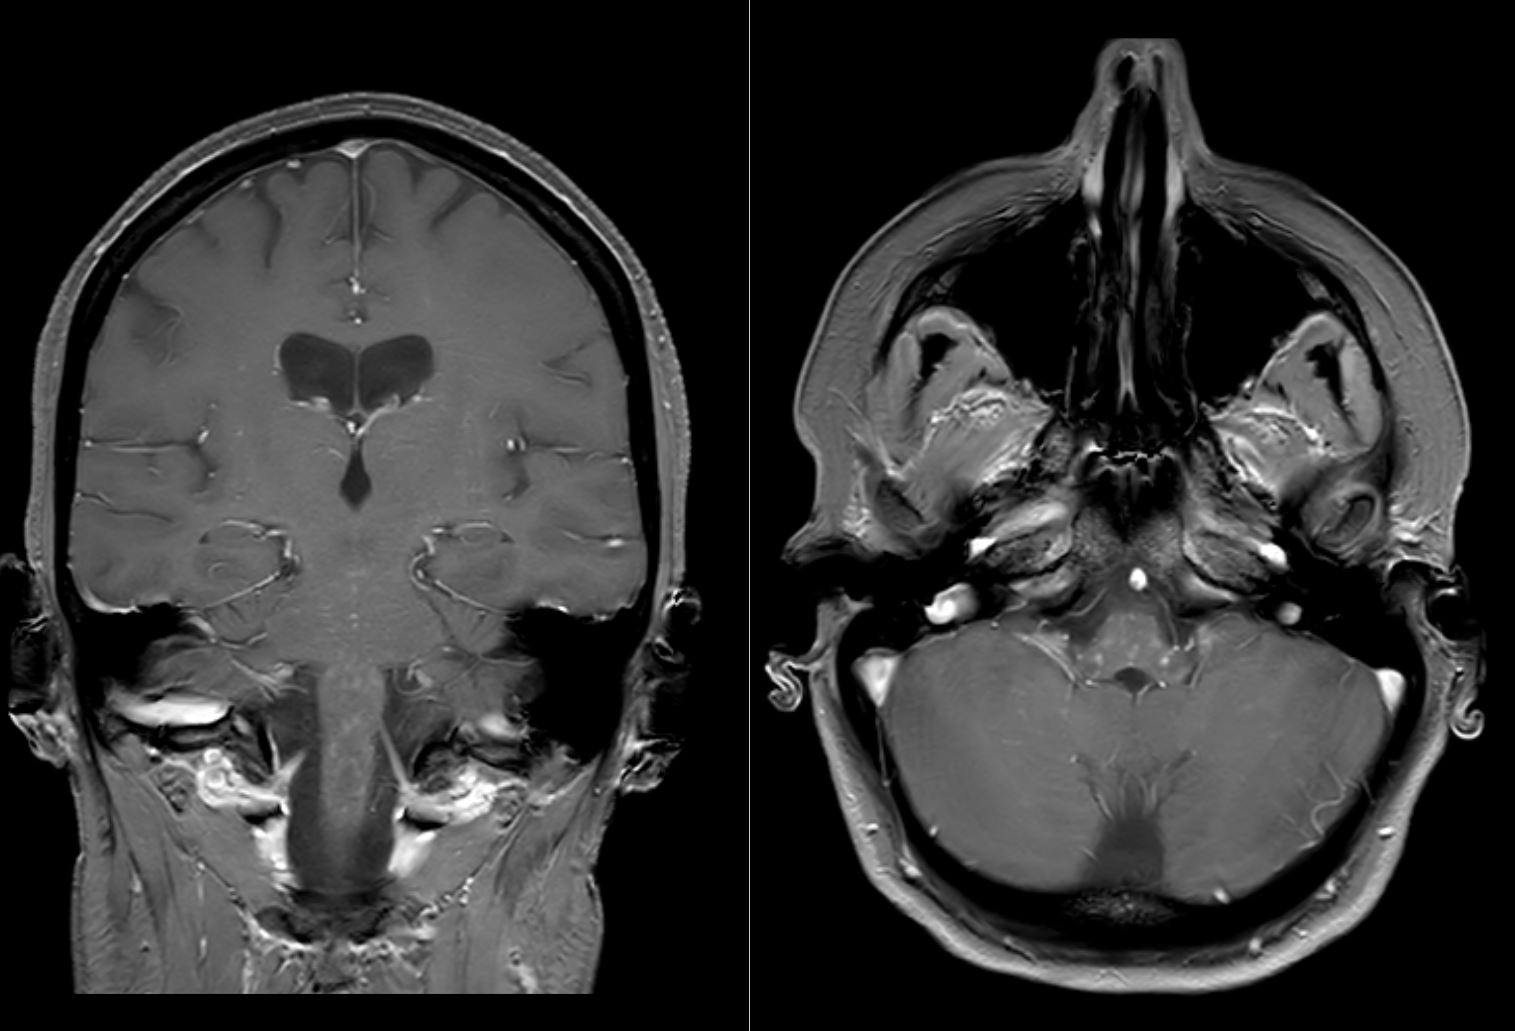

Clippers Mri : Living With CLIPPERS: MRI of CLIPPERS - And Now the ... : Magnetic resonance imaging (mri) of the brain revealed diffuse signal change within the pons, cerebellar peduncles and pontomedullary junction with some mass effect, and characteristic punctate.

Clippers Mri : Living With CLIPPERS: MRI of CLIPPERS - And Now the ... : Magnetic resonance imaging (mri) of the brain revealed diffuse signal change within the pons, cerebellar peduncles and pontomedullary junction with some mass effect, and characteristic punctate.. Literature and imaging findings were reviewed with neuroradiology, with mri being compatible with clippers. Magnetic resonance imaging (mri) is a medical imaging technique used in radiology to form pictures of the anatomy and the physiological processes of the body. .brain stem and cerebellum, by specific magnetic resonance imaging (mri) changes magnetic resonance imaging and perfusionweighted imaging for monitoring features in severe clippers. Index of biventricular interdependence calculated using cardiac mri: For the intrinsic small and thin structures of the tfcc, high field mr scanner e.g., 3 tesla mr scanner is ideally used to acquire a high spatial, high contrast imaging data (1,18).

Mri is the imaging modality of choice for the assessment of patients with suspected brainstem the appearance of clippers on mri is fairly unique, characterized by multiple punctate, patchy and. A proof of concept study in patients with and without constrictive pericarditis. Index of biventricular interdependence calculated using cardiac mri: Differential diagnosis, clinical and mri characteristics of clippers syndrome as well as treatment approaches are discussed. Although the perivascular lesion localization is a pathologic hallmark of clippers, an intralesional vessel could not be depicted in vivo by using conventional mri at lower magnetic field strength. Mini pathria and jennifer bradshaw. Pathria's specific areas of interest include musculoskeletal trauma, emergency radiology, and musculoskeletal mr imaging. Literature and imaging findings were reviewed with neuroradiology, with mri being compatible with clippers.

Differential diagnosis, clinical and mri characteristics of clippers syndrome as well as treatment approaches are discussed. Перевод статьи evans r.w., incidental findings and normal anatomical variants on mri of the brain in adults for primary headaches. Mini pathria and jennifer bradshaw. Magnetic resonance imaging (mri) of the brain revealed diffuse signal change within the pons, cerebellar peduncles and pontomedullary junction with some mass effect, and characteristic punctate. Index of biventricular interdependence calculated using cardiac mri: Literature and imaging findings were reviewed with neuroradiology, with mri being compatible with clippers. .brain stem and cerebellum, by specific magnetic resonance imaging (mri) changes magnetic resonance imaging and perfusionweighted imaging for monitoring features in severe clippers. Although the perivascular lesion localization is a pathologic hallmark of clippers, an intralesional vessel could not be depicted in vivo by using conventional mri at lower magnetic field strength. Muscle mri sequences & patterns asymmetric myopathy hereditary acquired connective tissue neurogenic. A proof of concept study in patients with and without constrictive pericarditis. Alibaba.com offers distinct smart medical diagnostic and advanced used mri for sale for hospitals and labs. Magnetic resonance imaging (mri) is a medical imaging technique used in radiology to form pictures of the anatomy and the physiological processes of the body. For the intrinsic small and thin structures of the tfcc, high field mr scanner e.g., 3 tesla mr scanner is ideally used to acquire a high spatial, high contrast imaging data (1,18).